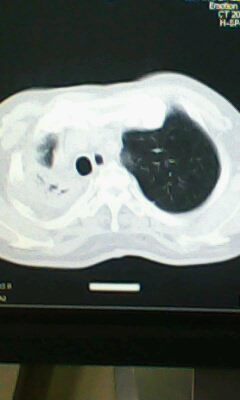

标题: CT25675:男 71 肺癌部分切除术后 3年 [打印本页]

标题: CT25675:男 71 肺癌部分切除术后 3年

1)两肺感染性病变。2)右侧胸膜增厚。3)冠状动脉及主动脉钙化。

术后改变,双肺内纤维索条影考虑与放疗有关。